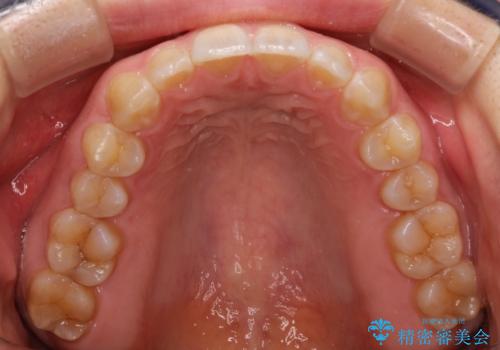

前歯の隙間を閉じたい インビザラインによる矯正

- 上下の前歯に隙間があるとのことで来院されました。

インビザラインにて隙間を閉じる矯正を行いました。

使用時間を守っていただけたので、比較的スムーズに矯正を終了することができました。